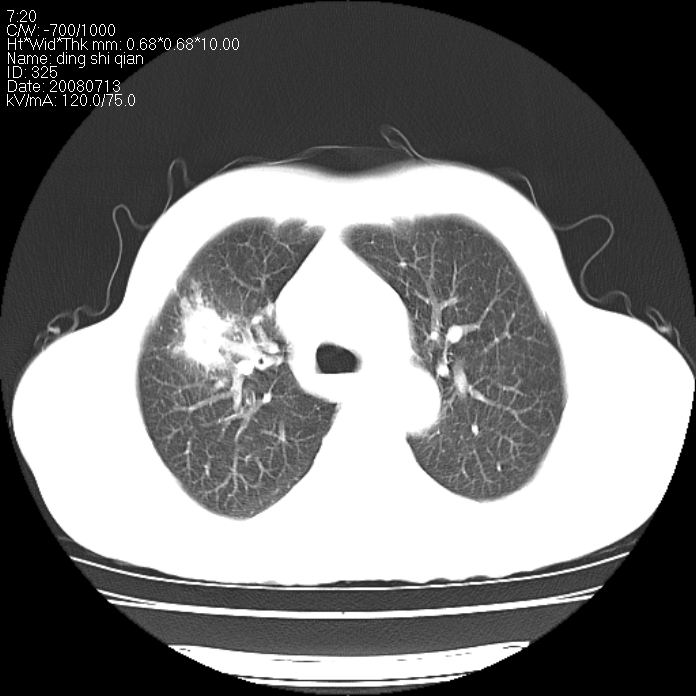

标题: CT14654:男 50岁 近来胸痛 [打印本页]

标题: CT14654:男 50岁 近来胸痛

右侧上肺块状软组织影,浅分叶,边缘毛刺证,与胸膜粘连,考虑:周围性肺癌

右侧上肺块状软组织影,浅分叶,边缘毛刺证,与胸膜粘连,考虑:周围性肺癌!支持!

典型右肺周围型肺癌

首先考虑周围性肺癌,建议强化或穿刺明确